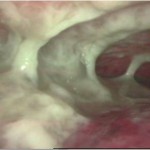

Acute Scrotum (Right scrotal Abscess)

Acute Scrotum